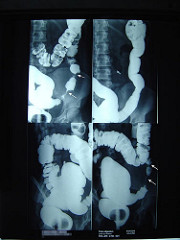

technorati tags: left bowel obstruction, mechanical obstruction, diverticulitis, intestinal obstruction, surgery, acute abdomen, abdominal, medicine, medicina, unbounded medicine